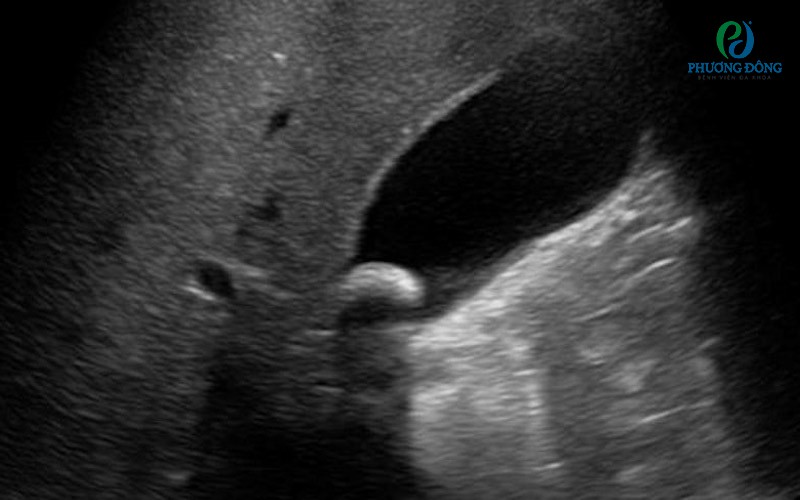

Hình ảnh siêu âm của túi mậtHình ảnh siêu âm của túi mật

Túi mật và đường mật

• Bệnh lý: Sỏi mật, viêm túi mật, polyp túi mật, u đường mật.

• Ý nghĩa: Phát hiện nguyên nhân gây đau bụng, vàng da, rối loạn tiêu hóa.